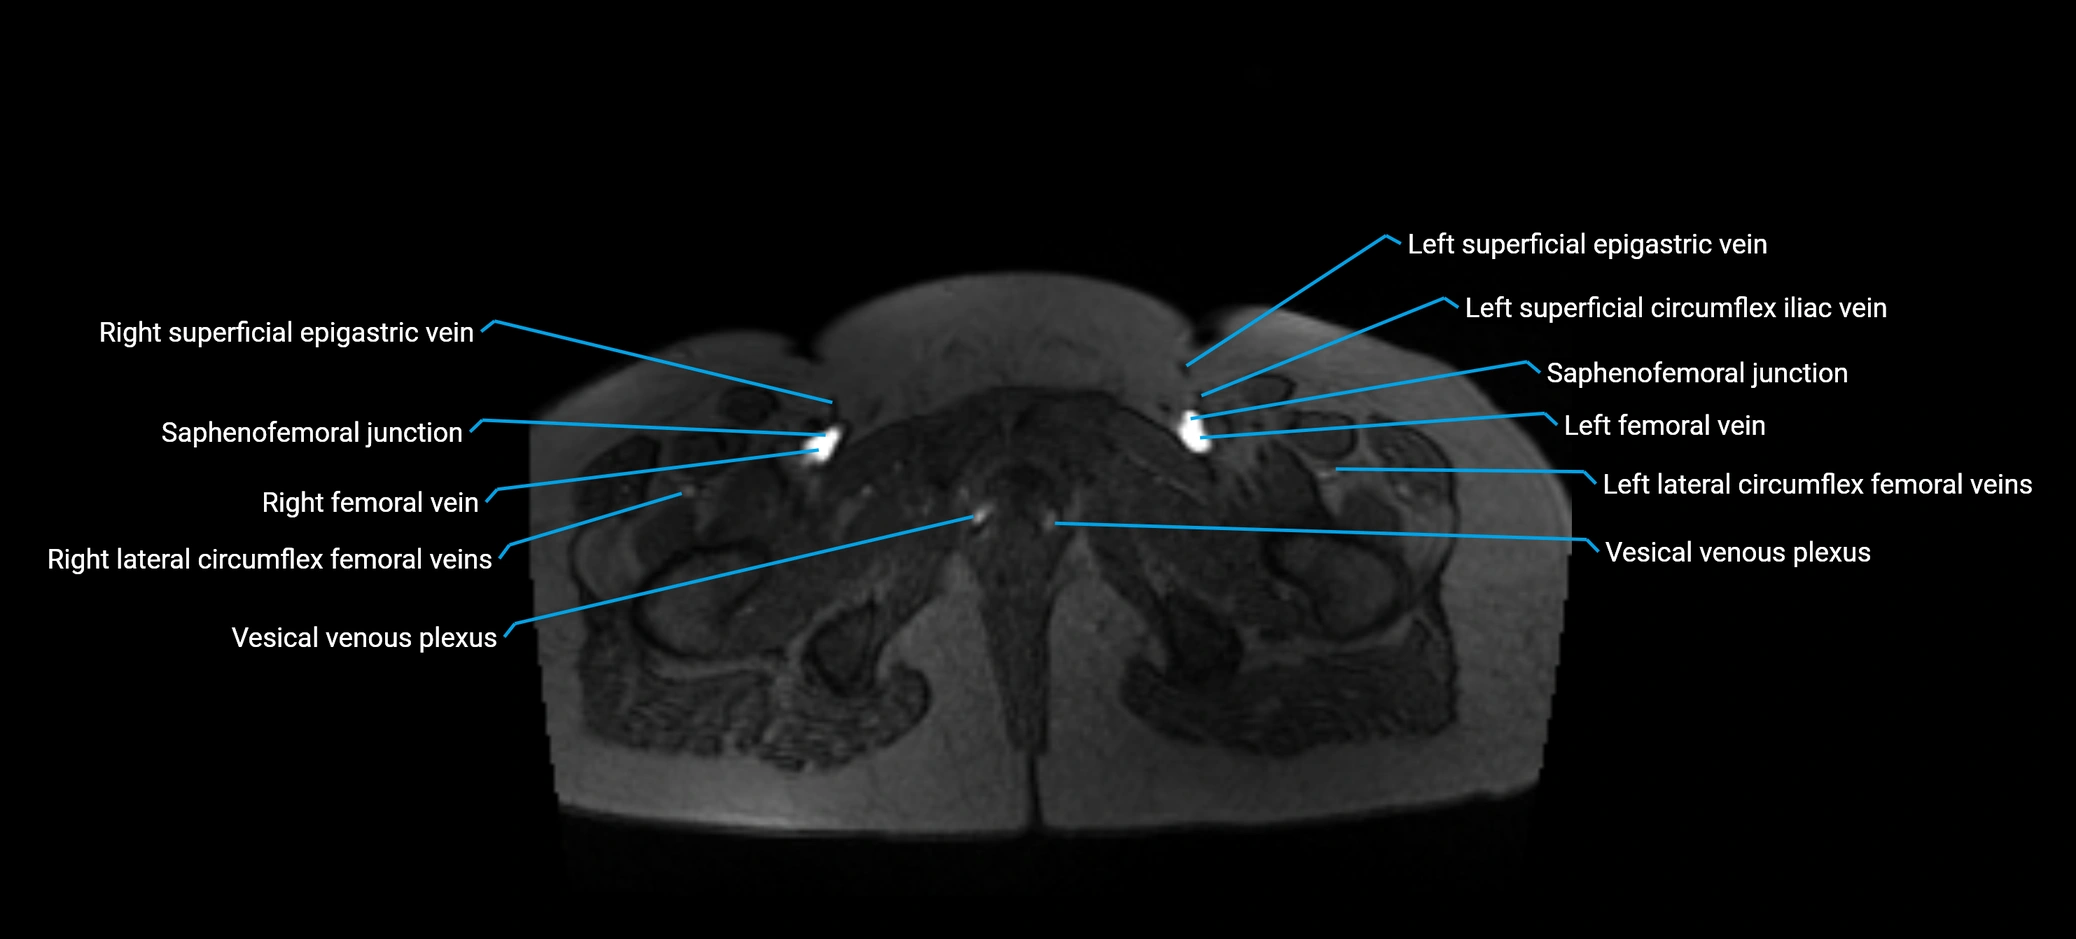

MRI image

image